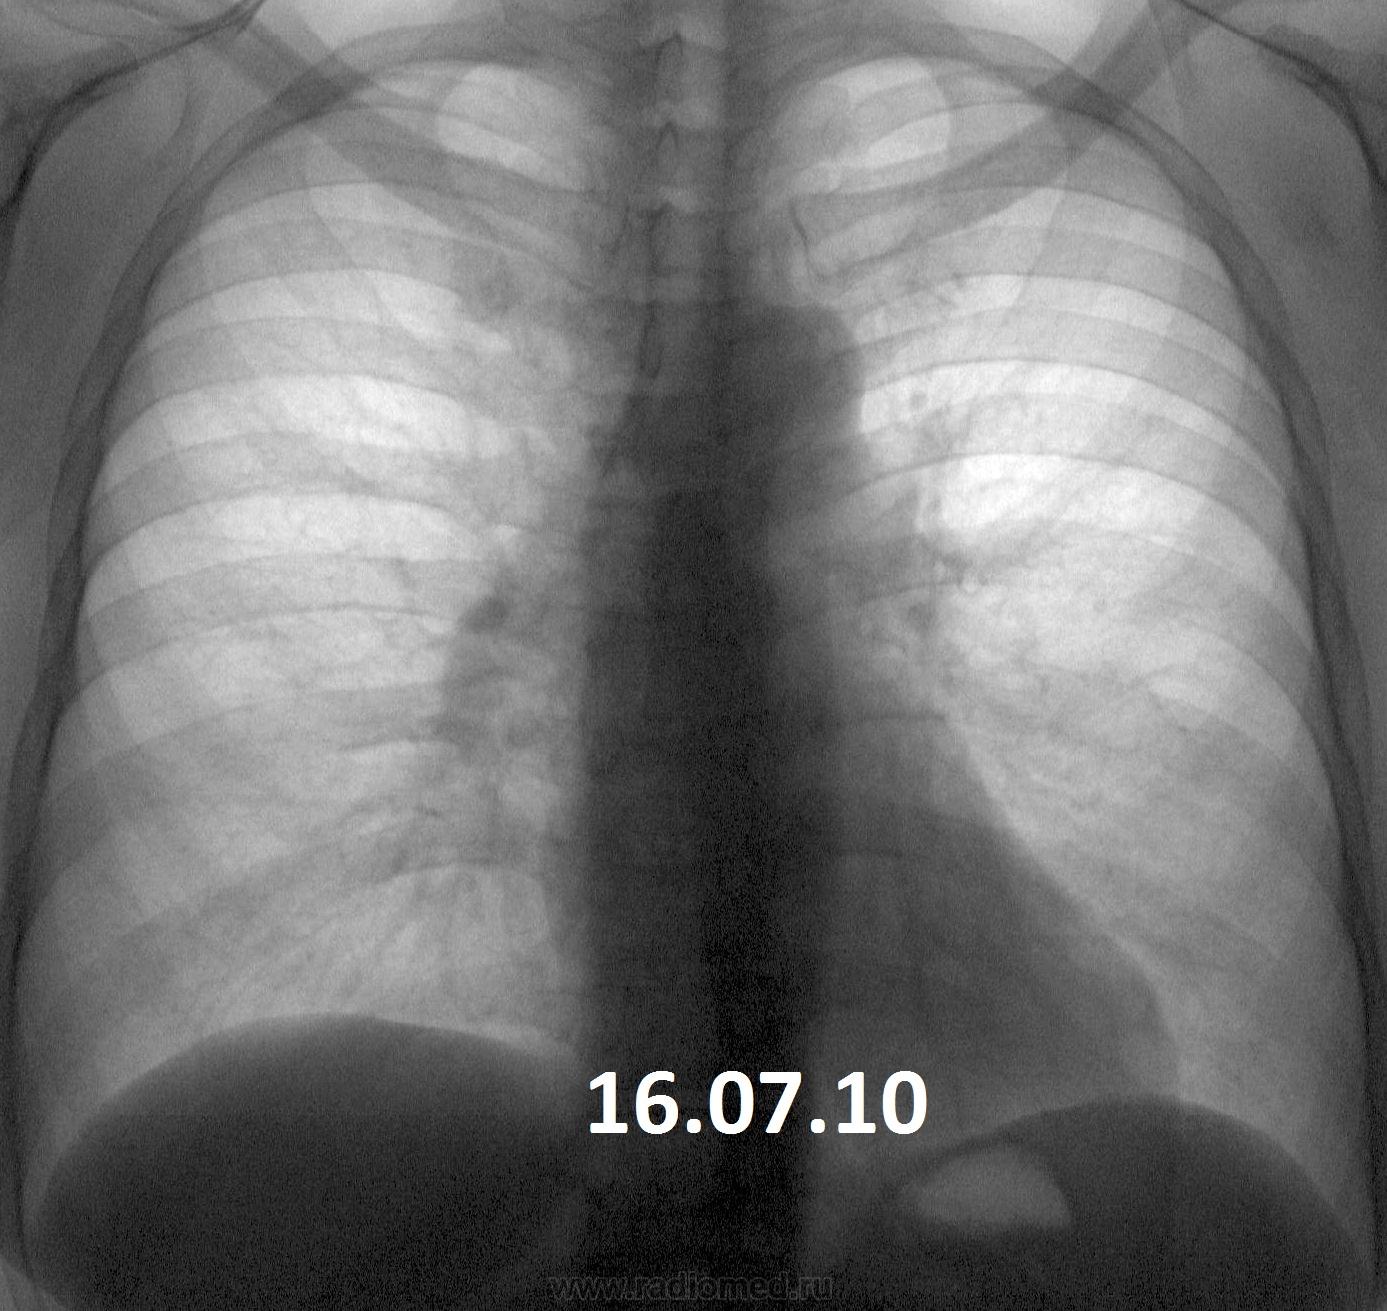

Два дня назад читал флюшки, показалось через чур много узелковых теней на фоне усиленного рис. Жалоб на "легкие" нет, но плохие анализы по "почкам". У мужа был (то ли умер, то ли развелась) ТБС. Придираюсь?

Похоже, не придираетесь. Очаги есть, диффузная деформация рисунка есть. Слоить надо.

Очагов как таковых не вижу, а медленно прогрессирующее изменение л/рисунка в средненижних отделах с преобладающим интерстициальным компонентом, по-моему, на лицо. +небольшая (возможно, кажущаяся) динамика расширения корня правого легкого. К норме отнести сложно. Нужен анамнез, исследование функции внешнего дыхания.

Изменены корни. Вероятней всего сердечные проблемы и изменение ЛР с этим и связано. Какой хоть возраст?

А может быть начало милиарного Тб?

Женщина 1958 г.р., профилактическая флгр., жалоб на ОГК не предъявляет. Есть же изменения в легких при заболевании почек, или эта картина никак к этому не лезет?

P.S. Не знаю почему, но на флюорографе - картина явно разнится м-ду годами, а за процедурами  сжатий и обработок изображений - изюминки потерялись.

А отчего бы не быть саркоидозу???

+1...очень похоже на медиастинально-легочную форму. Игорь Иванович, лучше перестрахуйся консультацией в ОТД.

Саркоидоз ВГЛУ и легких